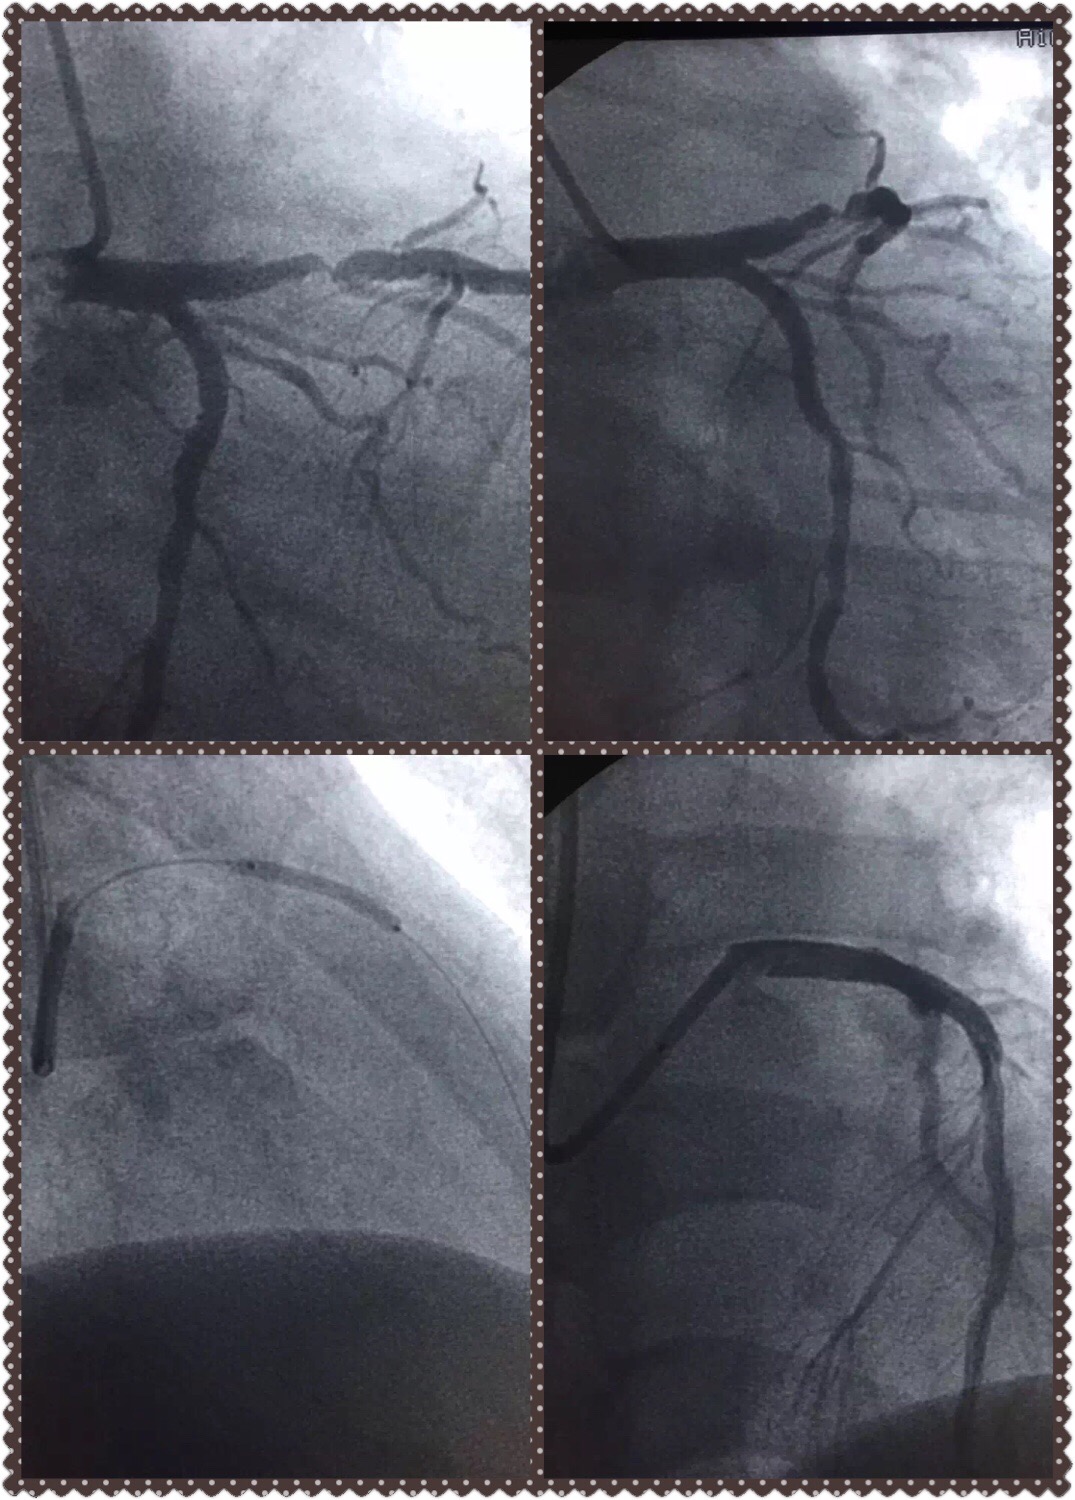

首先我想分享三个我们亲自经历的病友的故事。第一例,是我多年的朋友,并且还有几个共同的好友,45岁男性,已经有多次严重心绞痛症状,但听说"支架"不良传说,极其排斥支架,多次劝说后同意冠脉造影看看有多严重。造影发现前降支有近乎闭塞的局限病变。出现心梗的风险极高,非常适宜支架植入术。手术台上我们花了很长时间说服并且以朋友的名义担保。才接收了介入治疗。2年过去了,他才彻底消去疑虑。

第二例更加令人痛心,从河北农村来的66女性,有过脑梗史,因严重心绞痛转入我科,每步行十余步或上厕所就发作胸闷,一入院就一级护理,积极术前准备,两天后列入手术记划,但患者觉得自己″好多了",要先回家照顾老伴,顺便再凑点钱。无论如何劝说交待她的危险都不接收,因考虑到患者有可能转其医院手术,把方案详细交待后出院。悲哀的是第二天下午传来消,患者由于心梗死于家里。生命就这样在马上到岸时侯重返大海翻船。

第三例患者是一位下肢动脉闭塞的病例。某部局级退休老干部,并且托关系找院领导关心,男性,70岁,由于没人照顾,我在寻找陪护和术中都"特殊关照"。病情需要我们对右股浅动脉进行了顺行穿刺,闭塞病变再通,可能手术时间短,仅20分钟,患者非常满意,就以为没什么事。为了安全,还对穿刺点强化包扎。本以为"高级″干部会有很好的依从性。可是,这个老同志躺不住,非常好客,几小时之后就下床接待客人,没过多会竞然消失了。最后发现在陪另一批客人花园散步。我不得不"抓一个"看似稳重的探视客人了解他是否有精神心理问题,答案是没有。老先生的回答令我们哭笑不得:"我认错,但我相信你的权威和技术″。对他,我只能冒着被告壮的风险对他威逼反脸。